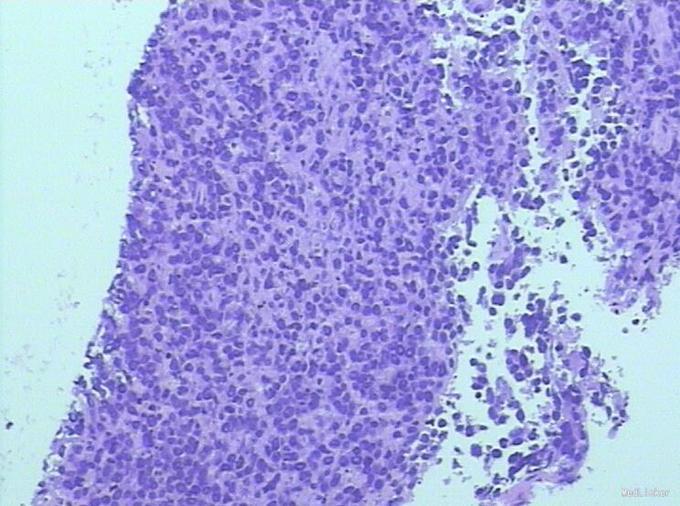

诊断:原发中枢神经系统淋巴瘤(弥漫大B细胞淋巴瘤,非GCB组) 治疗:入院行立体定向下左颞叶病灶活检术,病理:非霍奇金淋巴瘤,B细胞性,原发中枢神经系统弥漫大B细胞淋巴瘤,非GCB样免疫亚型。予替莫唑胺150mg d1-5口服和第1疗程HD-MTX治疗。